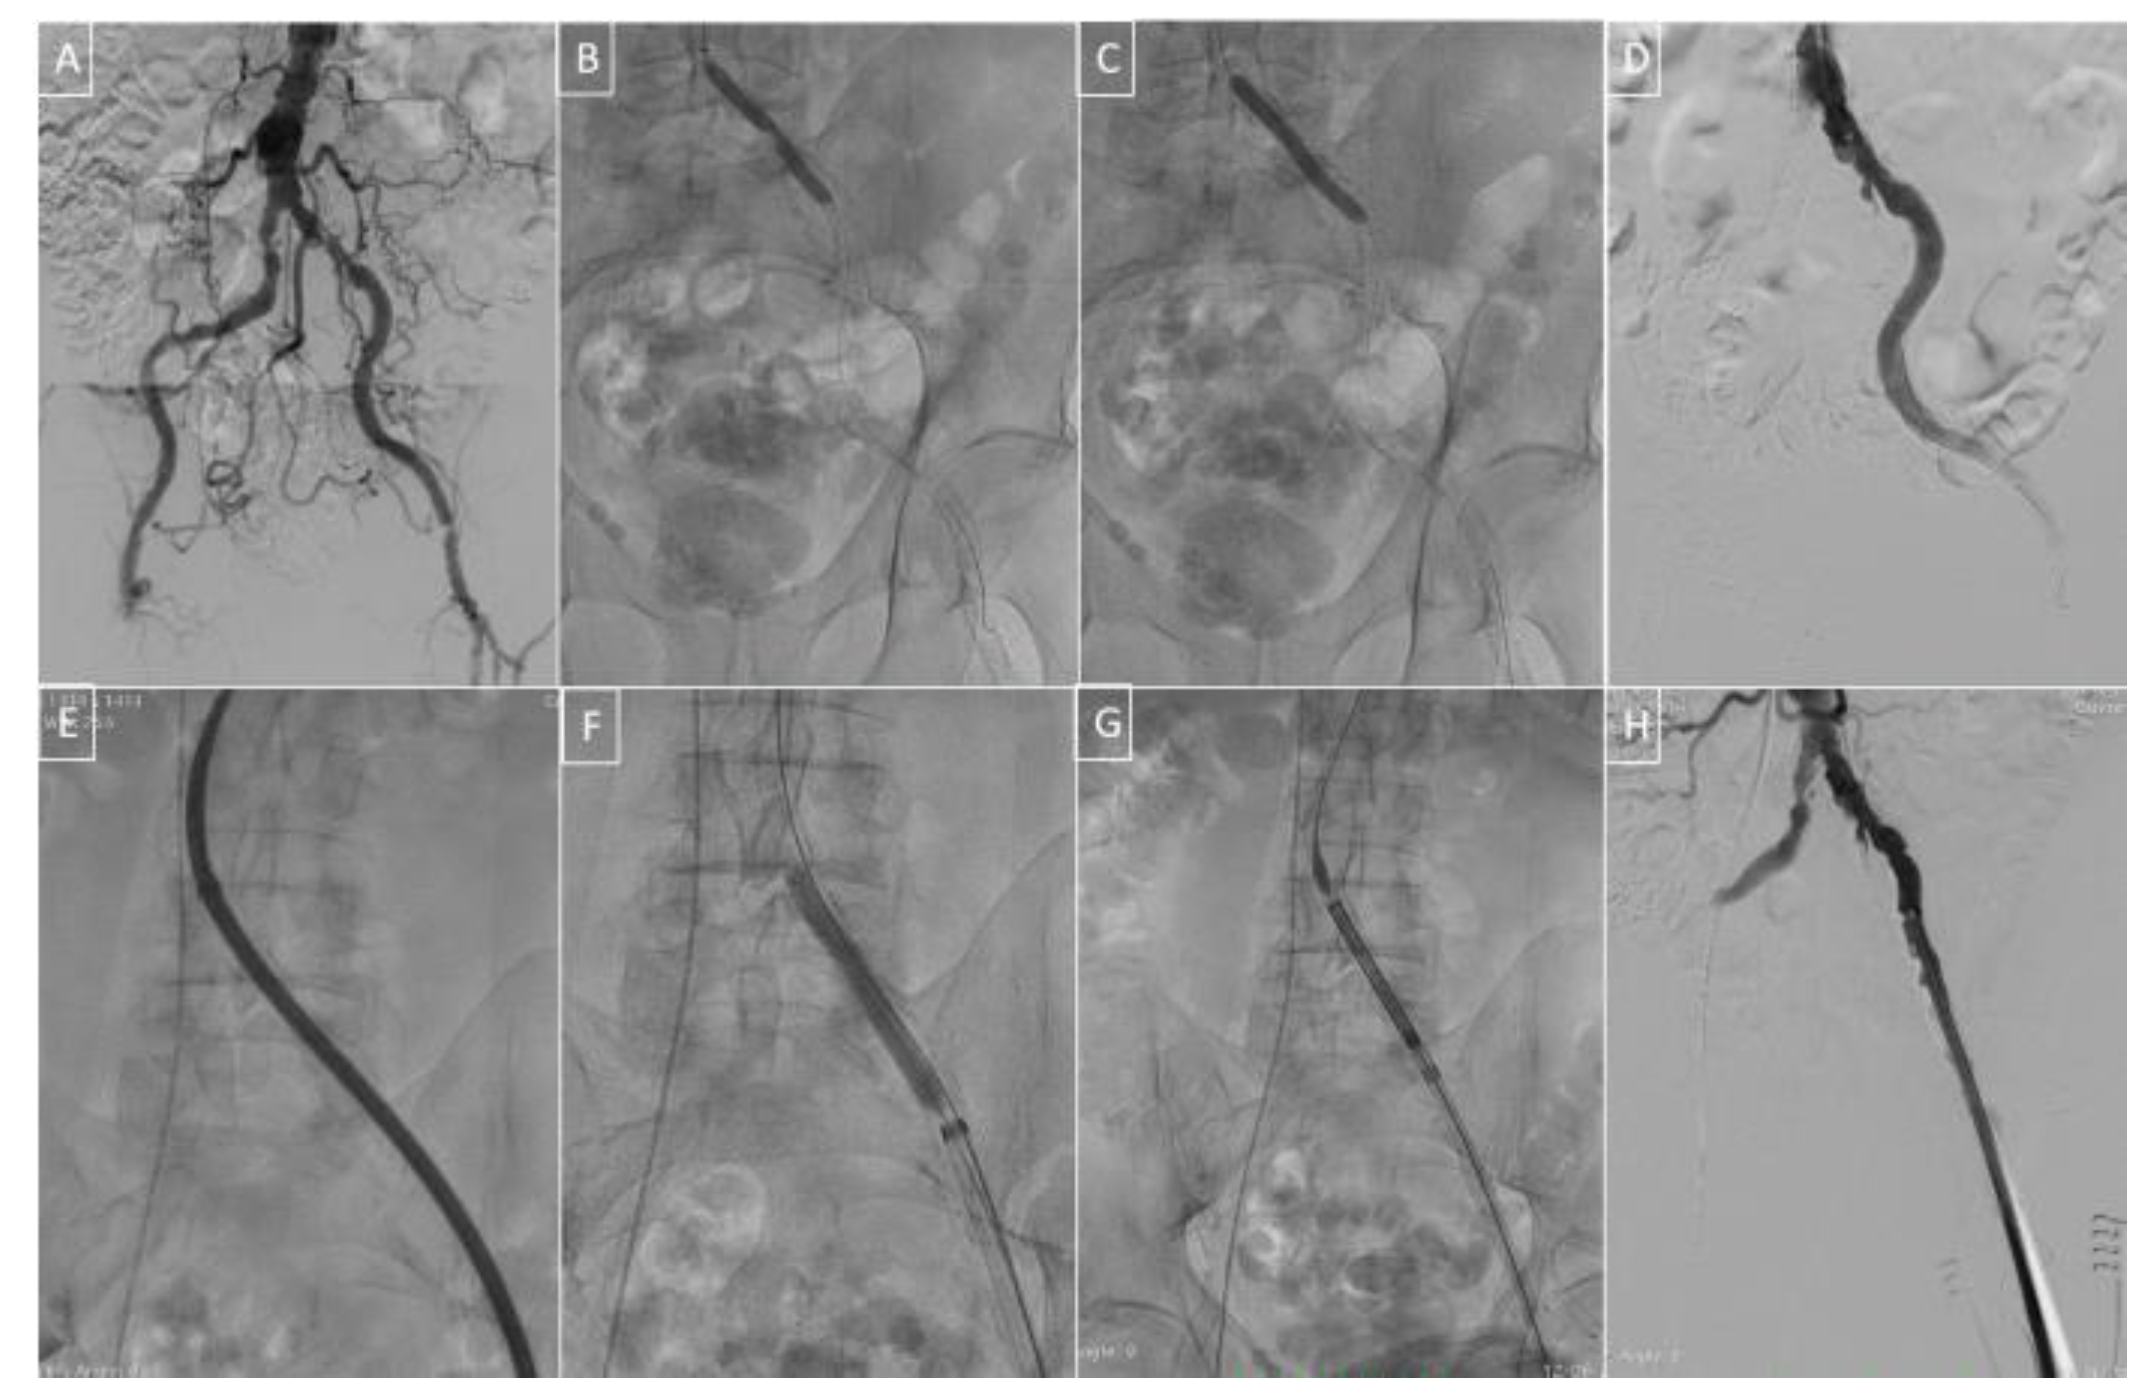

- Di Mario, C.; Goodwin, M.; Ristalli, F.; Ravani, M.; Meucci, F.; Stolcova, M.; Sardella, G.; Salvi, N.; Bedogni, F.; Berti, S.; et al. A Prospective Registry of Intravascular Lithotripsy-Enabled Vascular Access for Transfemoral Transcatheter Aortic Valve Replacement. Cardiovasc. Interv. 2019, 12, 502–504. [Google Scholar] [CrossRef]

- Ristalli, F.; Dini, C.S.; Stolcova, M.; Nardi, G.; Valente, S.; Meucci, F.; Di Mario, C. Role of Lithotripsy for Small Calcified Iliacs in the Era of Big Devices. Curr. Cardiol. Rep. 2019, 21, 143. [Google Scholar] [CrossRef]

- Di Mario, C.; Chiriatti, N.; Stolcova, M.; Meucci, F.; Squillantini, G. Lithotripsy-assisted transfemoral aortic valve implantation. Eur. Heart J. 2018, 39, 2655. [Google Scholar] [CrossRef] [PubMed]